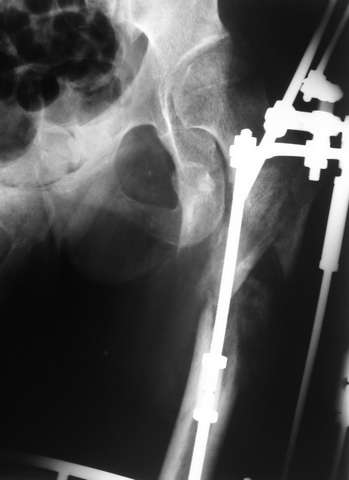

Мы закончили репозицию отломков бедренной кости в аппарате (рис. 1, 2) у нашей пациентки (http://weborto.net/forum/1200869039/index_html) и на прошлой неделе сделали ей вторую операцию. Штифт удалось ввести закрыто. Верхний шеечный винт держался очень плохо, поэтому мы его убрали и решили не ставить. Нижний держал очень плотно. Рентгенограммы после операции прилагаю (рис. 3,4). Пока не получилось сделать нормальный аксиальный снимок (больная с трудом сгибает и отводит ногу в тазобедренном суставе). Пока сделали боковую проекцию в положении на здоровом боку со сгибанием здоровой ноги.

Имя     : рис. 1.jpg

Тип     : image/jpeg

Размер  : 49856 байтов

Описание: отсутствует

Url     : http://weborto.net:8080/pipermail/ortho/attachments/20080216/c8b24fe3/attachment-0004.jpg